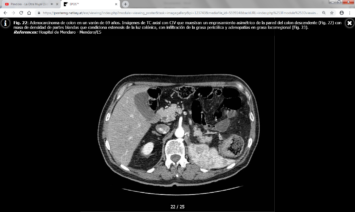

La TC juega un papel importante en el estudio de extensión del carcinoma colorrectal y en la detección de recurrencias.

Los hallazgos en TC incluyen una masa de densidad de partes blandas de contornos irregulares o un engrosamiento parietal focal asimétrico que condicionan estenosis de la luz colónica. Las masas de mayor tamaño pueden presentar un centro necrótico de baja atenuación y ocasionalmente pueden contener gas.